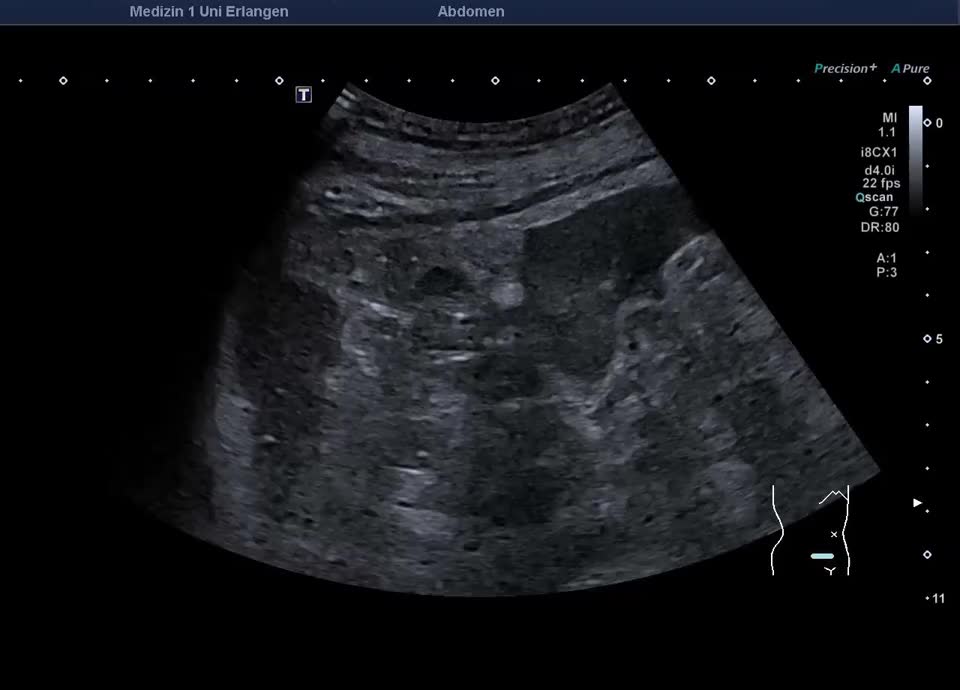

Retroperitoneum

• Psoas metastasis of urothelial carcinoma